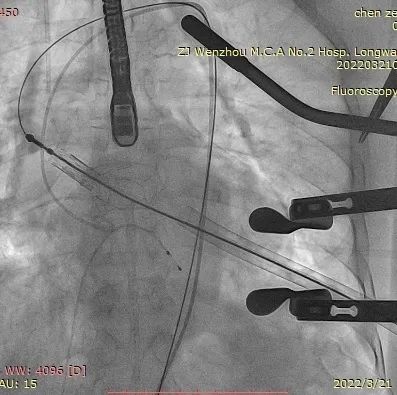

术中影像监护与评估(DSA&TEE)

瓣膜释放泥鳅导丝和单弯管过弓

加硬导丝建立轨道

介入器过瓣环平面

释放定位件

瓣膜入座

瓣膜自膨

松开锁丝,撤出输送器

DSA和TEE显示无瓣周漏,瓣膜位置、形态良好